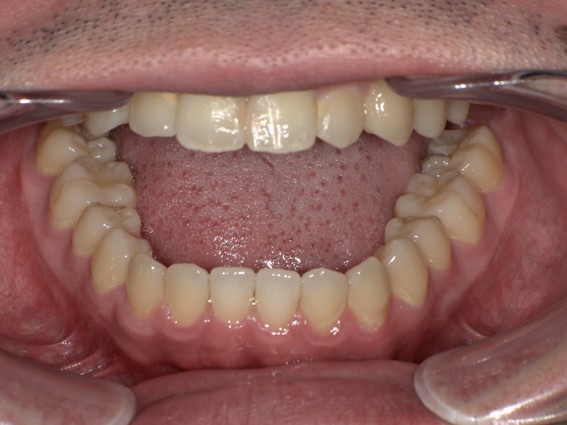

| 主訴 | 口元がでている、口が閉じずらい、上の歯と下の歯のがたつき、顎がない。 |

| 治療内容 | 上下のワイヤー矯正を行いました。 |

| 治療費 | 880,000円(税込) |

| 治療期間 | 28ヶ月 |

| 治療回数 | 28回 |

| 想定されたリスク | 知覚過敏・咬合痛・歯肉退縮・歯髄壊死・歯髄充血のリスクがありました。 |

以前骨切りを勧められたことがあるという方でしたが、抜歯矯正で口元の突出や顎のしわを改善しました。上唇の厚みや頬の高さを考慮し、老けた印象にならないよう配慮。お顔全体のバランスと年齢に合わせた治療を行いました。